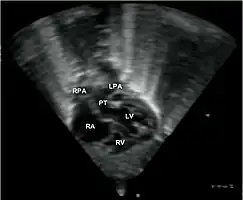

Echocardiography of a complex transposition with a ventricular septal defect and pulmonary stenosis.

Abbreviations: LV and RV=left and right ventricle, PT=pulmonary trunk, VSD=ventricular septal defect, PS=pulmonary stenosis.

Echocardiogram in transposition of the great arteries. This subcostal view shows the left ventricle giving rise to a vessel that bifurcates, which is thus identified as the pulmonary artery.

Abbreviations: RA=right atrium, RV=right ventricle, LV=left ventricle, PT=pulmonary trunk, LPA and RPA=left and right pulmonary artery.